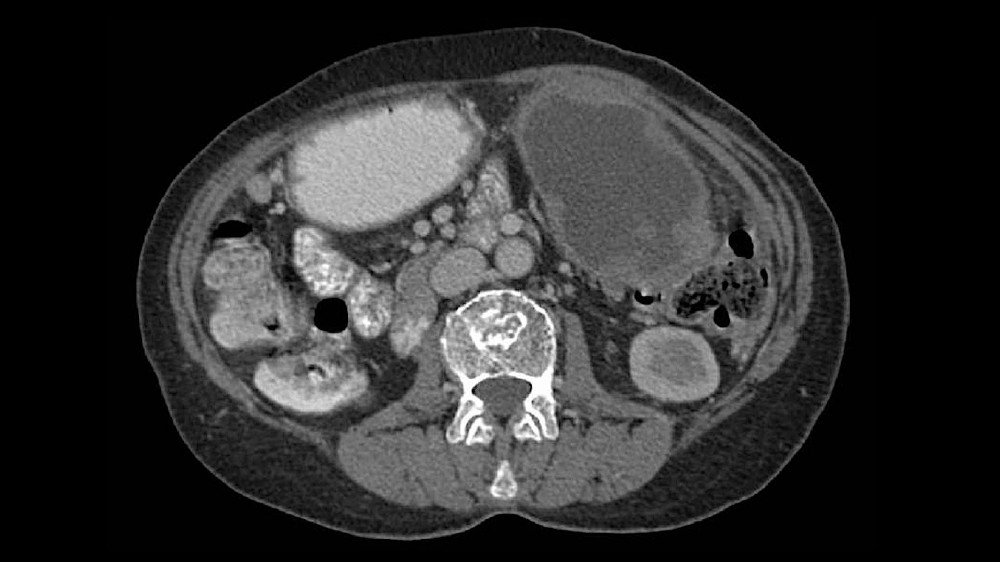

腹圍增加或腹水(液體積聚)造成腫脹

因大量腹水而導致嚴重且明顯的腹部腫脹

新陳代謝指標增加,顯示生物侵襲性(透過 PET 掃描可檢測到葡萄糖攝取率升高)。

由於腹膜廣泛擴散,腹水形成變得突出